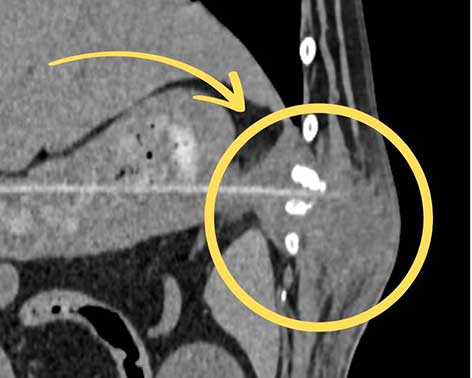

An einer betroffenen Rippe zeigten sich dadurch bereits beginnende Auflösungserscheinungen.

In der 3-D-Darstellung des CTs ist die Beschädigung der Rippe gut zu erkennen.

Ein anschließendes CT bestätigte den Verdacht und zeigte das Ausmaß der inneren Verletzung: Ein rund 17 Zentimeter langer Holzspieß hatte sich durch die Magenwand gebohrt und war weiter durch die Bauchwand gewandert. Besonders dramatisch: Der Fremdkörper war inzwischen vollständig eingewachsen, das umliegende Gewebe stark entzündet und verändert. An einer betroffenen Rippe zeigten sich dadurch bereits beginnende Auflösungserscheinungen.